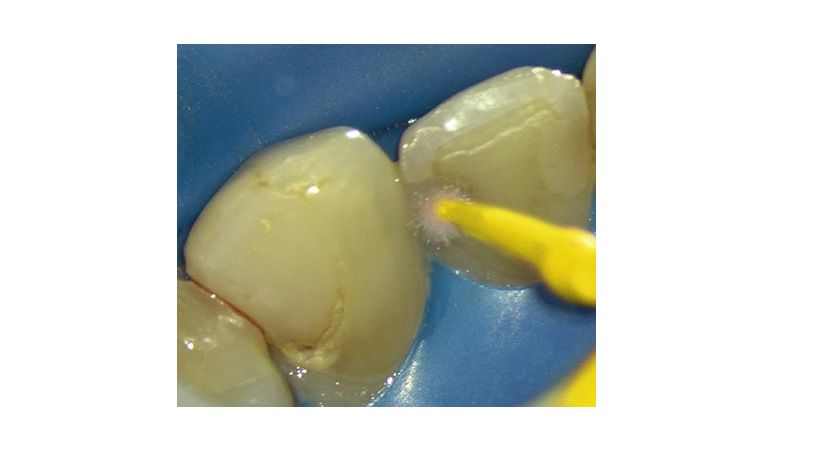

Materiales restauradores bioactivos en odontología

Una revisión integral de los mecanismos, aplicaciones clínicas y direcciones futuras